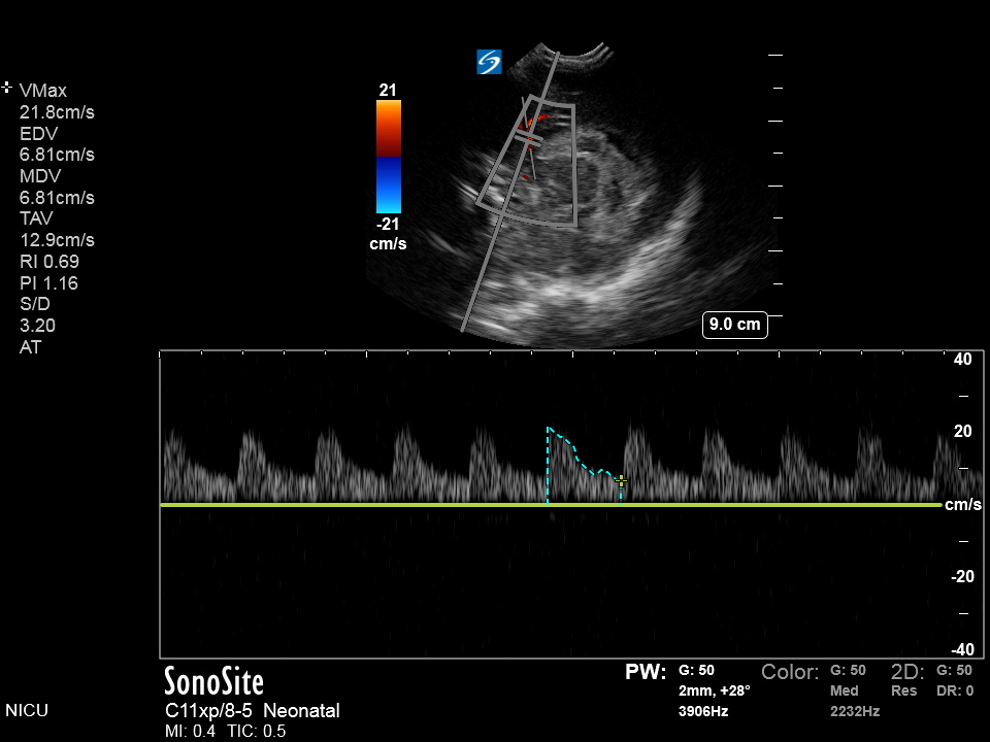

Neonatology Hydrocephalus Compression Test B Image